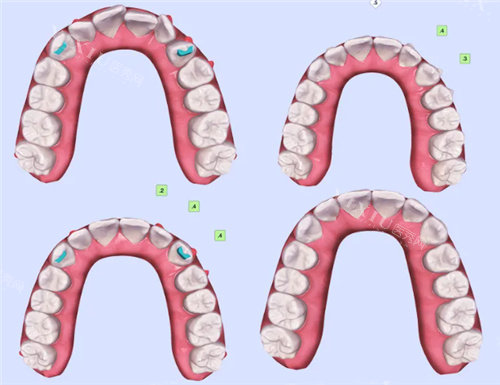

太原纺织医院口腔科牙齿矫正价格表

传统金属托槽矫正:4980 元起

金属自锁托槽矫正:8800 元起

沪鸽隐形矫正:10800 元起

时代天使隐形矫正:15000 元起

青少年金属托槽矫正:8800 元起,含保持器 1 副

青少年陶瓷半隐形矫正:12800 元起,含保持器 1 副

成人隐适美 Go 隐形矫正:19800 元起,支持多期付款

成人时代天使冠军版:26800 元起,支持多期付款

儿童早期干预矫正:6800 元起,正颌术前术后正畸询问免费